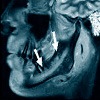

МРТ височно-нижнечелюстных суставов

МРТ височно-нижнечелюстных суставов. Метод клинической радиологии, позволяющий изучать парные височно-нижнечелюстные суставы путем регистрации ядерного магнитного резонанса на ядрах атомов водорода для получения высокоточных изображений тканей. В ходе исследования выявляются суставные поверхности костей, суставных дисков, связок, суставной полости и окружающих мягких тканей. МРТ височно-нижнечелюстных суставов имеет диагностическое значение при выявлении остеоартрита, артрита, синовита, анкилоза, опухолей, пороков развития височно-нижнечелюстного сустава, травм челюсти. Исследование можно заказать при планировании ортодонтического и ортопедического лечения. Функциональные тесты должны выполняться во время процедуры (сканирование выполняется с закрытым и открытым ртом), в зависимости от показаний применяется контрастное усиление.